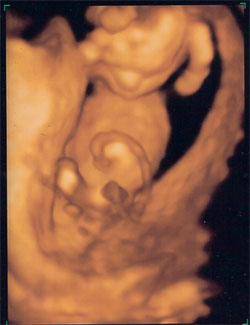

Igaz, nekem még nagyon pici a babám, de azért mutathatom? :wink: Tegnap, hirtelen felindulásból felhívtam egy 4D-s céget, hogyha karácsony előtt adnak időpontot, megyek, ha nem, akkor valahogy bírok a fenekemen maradni. Nos, én tegnap estére kaptam is időpontot, úgyhogy végre megnézhettem, hogy ver a kis szíve, és mit is csinál odabent a 14 hetes kislányom (mert a neme is kiderült :D ). Olyan boldog vagyok, bár hallottam, hoyg enm lesz oylan élvezhető, mint amikor már mimikája, arcvonásai vannak - de én így is nagyon elégedett vagyok, hogy él, kapálózik, ficánkol. és Kislány, ahogy éreztem. Kép